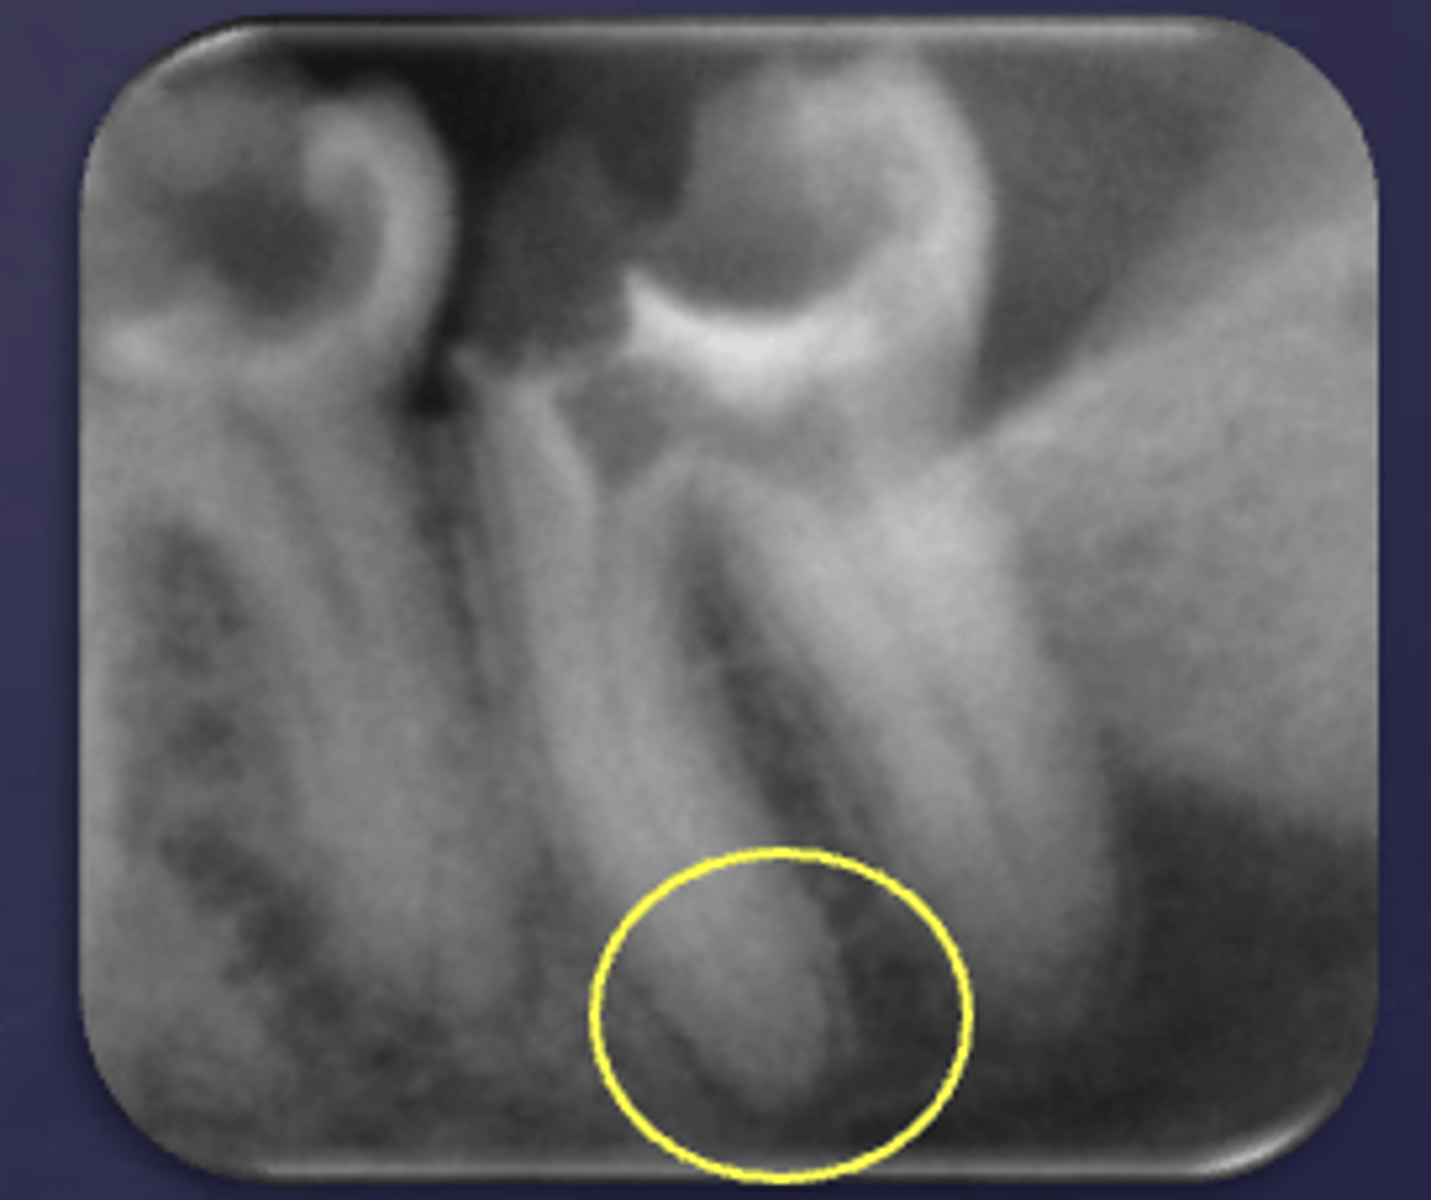

What type of change is seen in this radiograph?

early change (apical periodontitis #21)